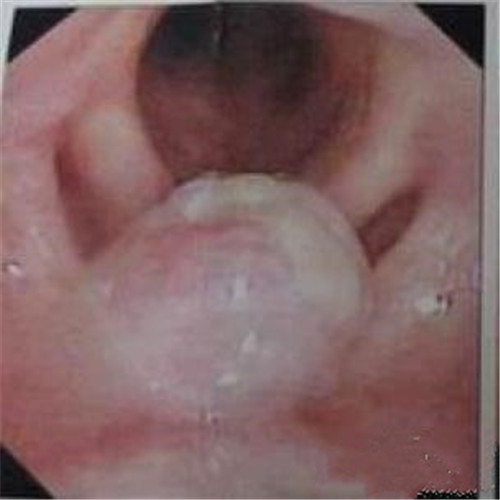

呼吸道感染兩側發炎